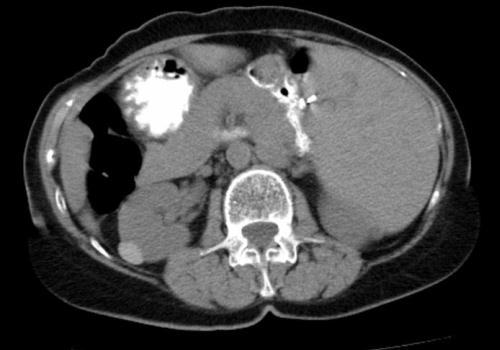

Гиперэхогенные включения в почках представляют особый интерес, так как могут являться признаками довольно широкого спектра заболеваний.

Псаммомные (или псаммозные) тела представляют собой множественные гиперэхогенные включения в почках округлой формы, размерами чаще всего от 0,5 мм до 3 мм. Структура телец слоистая, состоят они из белково-липидного компонента, инкрустированного солями кальция и фосфора. В норме такое образование может определяться в мозговых оболочках и некоторых сосудах, однако расположение их в почечной ткани может (но не всегда) указывать на наличие злокачественного образования, чаще всего – папиллярной карциномы. Наблюдение и лечение данной патологии ведёт врач-нефролог либо уролог.

На УЗИ псаммомные тела представляют собой россыпь ярких точечных структур мелкого размера, не имеющих акустической тени (симптом звёздного неба). Данные образования имеют наибольшую акустическую плотность среди всех тканей человеческого организма, поэтому их отчётливо видно на фоне любого органа. Псаммомные тельца располагаются не только в ткани опухоли (хотя их концентрация в ней значительно выше), но и по периферии от неё и в лимфатических узлах, находящихся поблизости.

Определение большого количества ярких мелких точечных эхоструктур в почечной ткани является одним из наиболее достоверных ультразвуковых признаков онкологического новообразования. В случае их визуализации необходимо особо тщательное исследование почечной ткани и близлежащих структур.

Крупные эхоплотные образования, дающие акустическую тень

В подавляющем большинстве случаев так выглядят конкременты почек (камни, макрокальцификаты). Подобную картину может давать и склерозированный, вследствие воспалительного процесса, лимфатический узел в области почки. Застарелые почечные гематомы также могут кальцифицироваться и имитировать УЗИ-признаки почечнокаменной болезни. Почечнокаменная болезнь лечится нефрологами и урологами.Чаще всего назначается специальная диета, ряд медицинских препаратов для растворения камней, санаторно-курортное лечение. Производится периодический ультразвуковой контроль, который отображает динамику состояния гиперэхогенных включений в почках. Хирургическая операция назначается только в крайних случаях – при обструкции мочевыводящих путей, повторяющихся мучительных болях, присоединении инфекции.

Крупные равномерно-эхоплотные образования без акустической тени

Чаще всего так выглядят доброкачественные образования почек – фибромы, гемангиомы, онкоцитомы. После тщательного обследования пациента и сдачи ряда лабораторных анализов, новообразования почек удаляются хирургическим путём методом резекции или частичного иссечения с последующей обязательной биопсией операционного материала.

Яркие точечные гиперэхогенные включения в почках, не имеющие акустической тени

В данном случае имеется два варианта. Первый – множественные безобидные кальцификаты, мелкие камни почек, почечный “песок”. Второй вариант – мелкие включения, размерами до 3 мм очень высокой эхоплотности – псаммомные тела, на которых хотелось бы остановиться поподробнее.